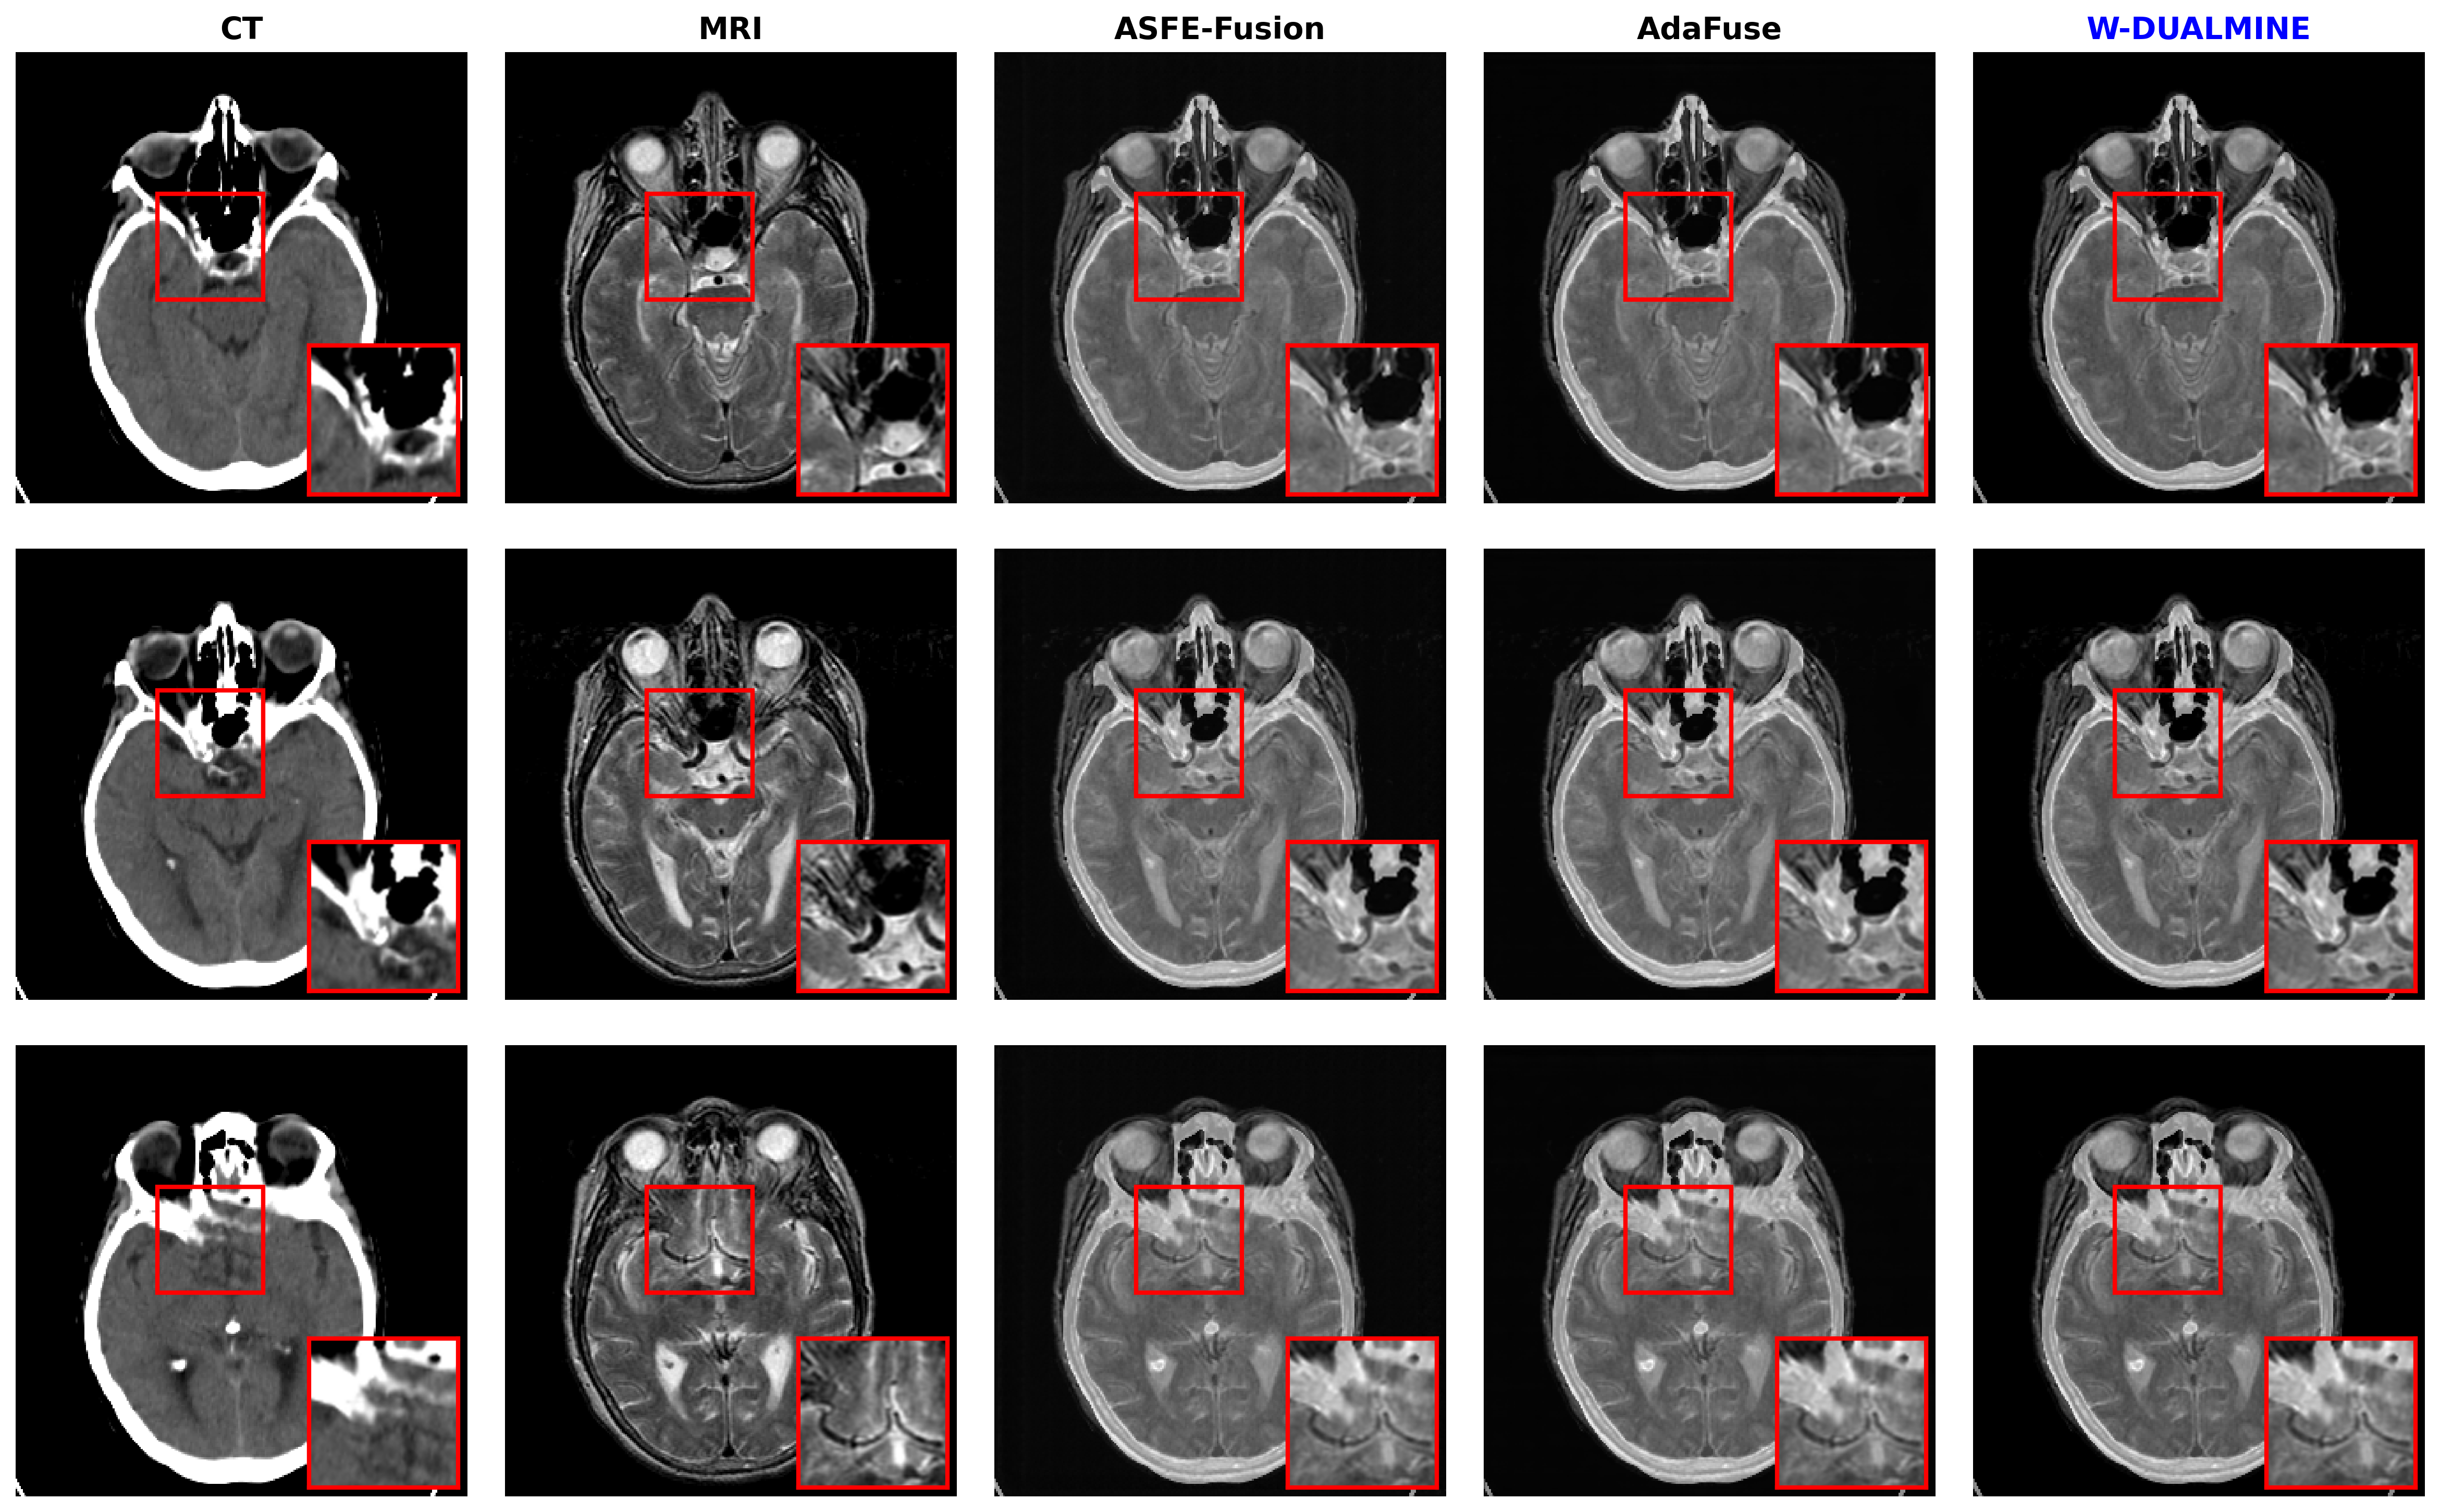

5.3.1 Results on CT–MRI Dataset

The CT–MRI task involves integrating high-contrast bone structures (CT) with soft-tissue details (MRI). The quantitative results are presented in Table 1.

Analysis: As observed in Table 1, W-DUALMINE achieves the highest scores in MI (3.60593.6059) and CC (0.83080.8308). This validates that the Residual-to-Average strategy effectively anchors the fused image to the statistical distribution of the sources. While ASFE-Fusion achieves higher Entropy (5.48555.4855), it yields a lower PSNR (63.988463.9884) and significantly lower FMI (0.40660.4066). High entropy coupled with low feature mutual information often indicates the amplification of noise rather than true information content. This method’s superior PSNR and FMI confirm that W-DUALMINE preserves actual anatomical edges with higher fidelity.

Refer to caption

Figure 3: Qualitative comparison on the CT–MRI fusion task. From left to right: CT image, MRI image, ASFE-Fusion, AdaFuse, and W-DUALMINE. Red boxes highlight regions of interest for detailed comparison. The proposed method preserves sharp CT structures while maintaining MRI soft-tissue contrast.

As shown in Figs. 35, W-DUALMINE produces visually superior fusion results across all modalities. The proposed method achieves better structural clarity and functional consistency than ASFE-Fusion and AdaFuse, particularly in highlighted regions.